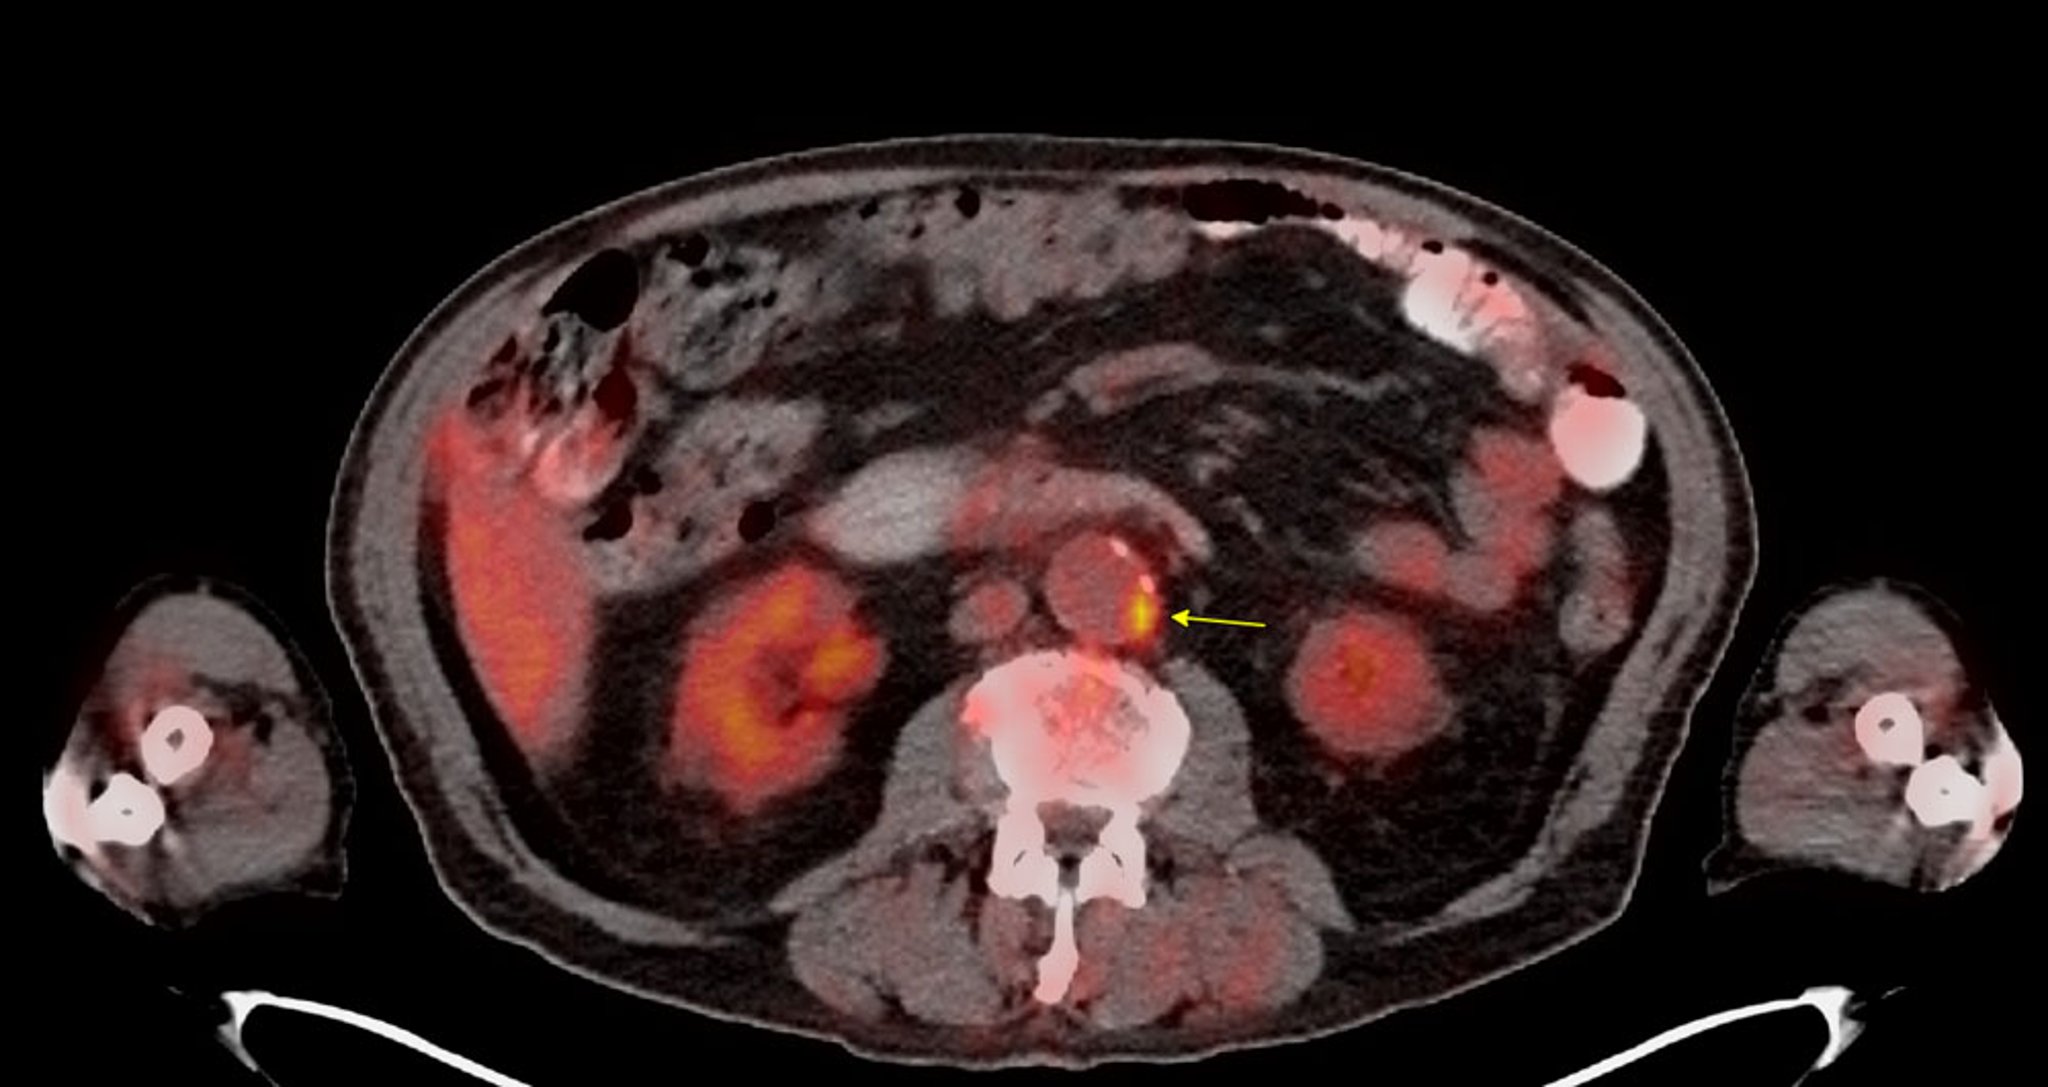

• Positron emission tomography (PET) molecular imaging: This technique uses molecular imaging tracers to detect metabolic activity of atherosclerotic plaques (F18-fluorodeoxyglucose [FDG]) or microcalcifications (F18-sodium fluoride).: This technique uses molecular imaging tracers to detect metabolic activity of atherosclerotic plaques (F18-fluorodeoxyglucose [FDG]) or microcalcifications (F18-sodium fluoride).